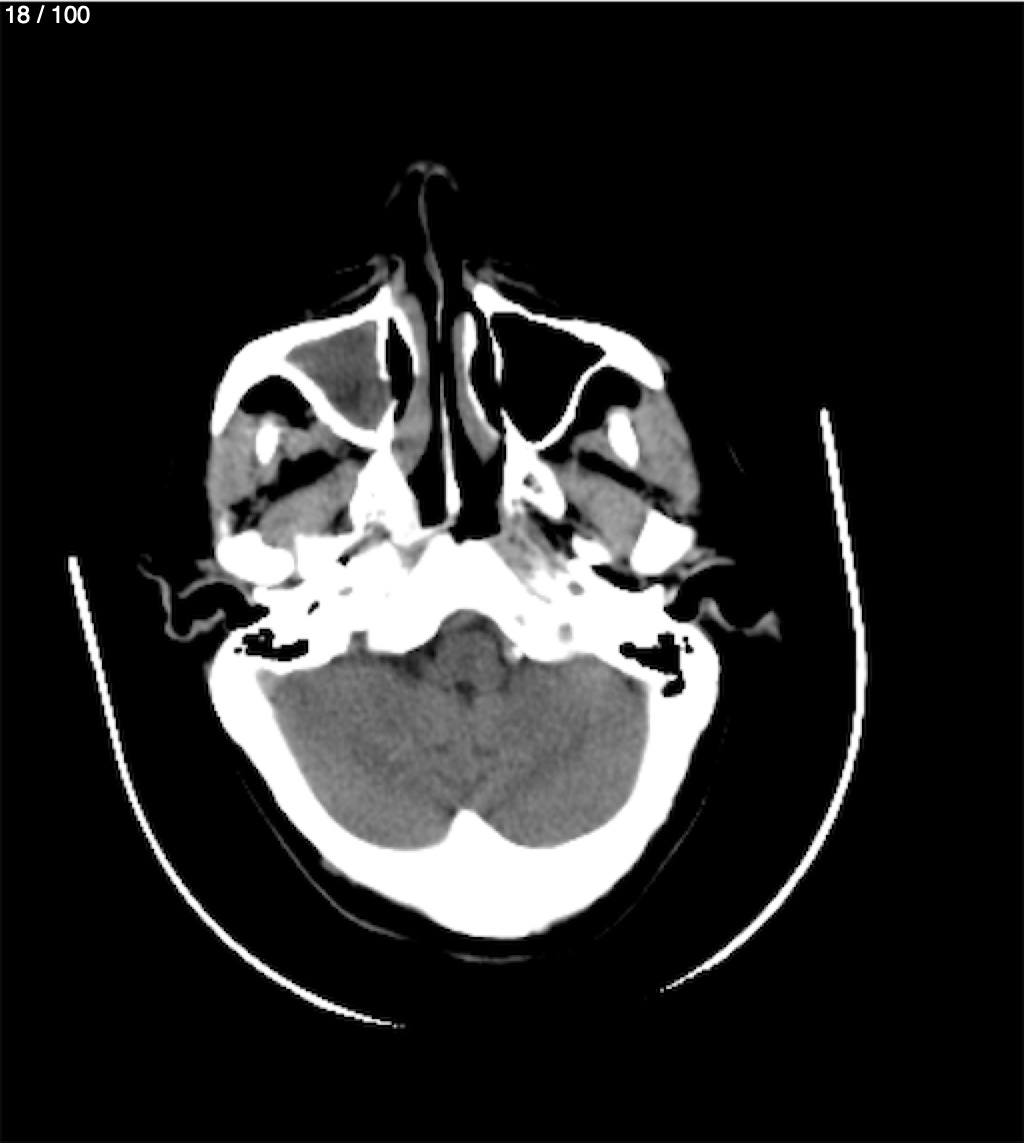

Valentin Perez Gomez 69A - T.C Craneo